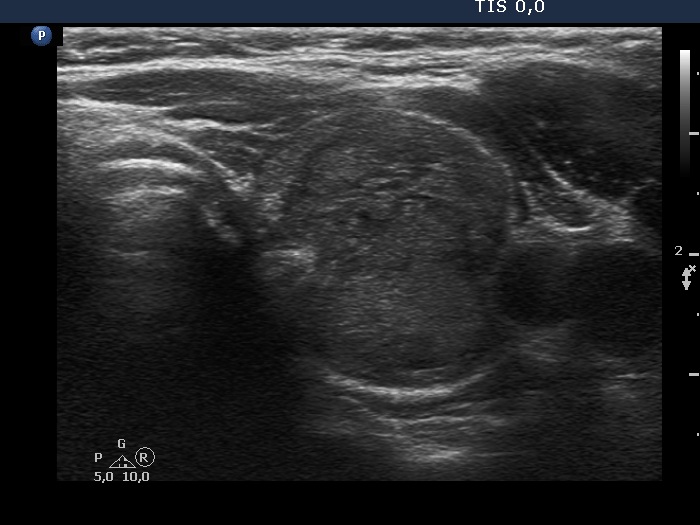

The echogenicity of the nodule - case 2067 (ultrasonographic picture 5)

Right lobe, longitudinal scan